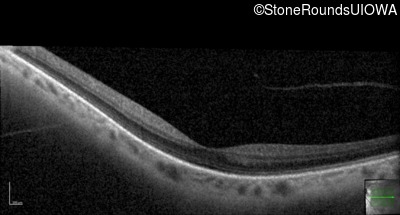

Age at visit: 41 years (Visit 2)

OD OS

This 41 year old woman was highly myopic as a child and experienced a rhegmatogenous retinal detachment OS at age 20.

Refraction OD:     -17.25 +1.00 x 93

Refraction OS:     -18.25 +3.50 x 56